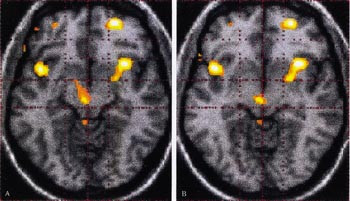

PET (positronemisjonstomografi)-undersøkelser har nylig vist en aktivering av hypothalamus på smertesiden under anfall med clusterhodepine (21). Man kunne lokalisere dette området til grå substans i hypothalamus, svarende til nucleus suprachiasmaticus (hvor biorytmer genereres) (fig 1) (22). Dette området blir ikke aktivert ved andre smertetilstander, som for eksempel migrene, og ikke etter injeksjon av capsaicin i pannen. Man så heller ikke slik aktivering i remisjonsfasen. Senere har man vist tilsvarende funn under et spontant anfall (Goadsby PJ, personlig meddelelse). Nylig har MRI-basert morfometri vist strukturelle forandringer i hypothalamus i det samme området (23).